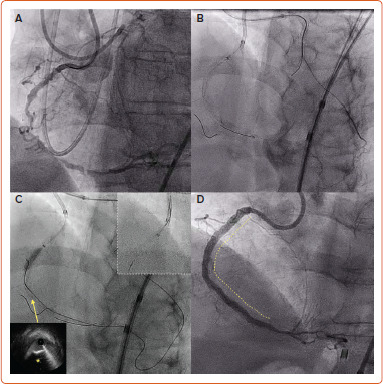

Despite early stagnation in success rates for percutaneous coronary intervention for chronic total occlusion with the traditional antegrade wiring approach, the introduction of dissection/re-entry techniques and the retrograde approach opened new avenues for operators to tackle more complex occlusions. Dissection/re-entry techniques (both antegrade and retrograde) are commonly used in angiographic scenarios characterised by long, tortuous and calcified occlusions, as well as in those with proximal cap ambiguity. Familiarity and comfort using the extraplaque space (with either an antegrade or retrograde approach) have become fundamental to achieving safe and effective recanalisation of complex chronic total occlusions. This review provides an overview of different contemporary antegrade and retrograde dissection re-entry techniques and their acute and longer-term outcomes.